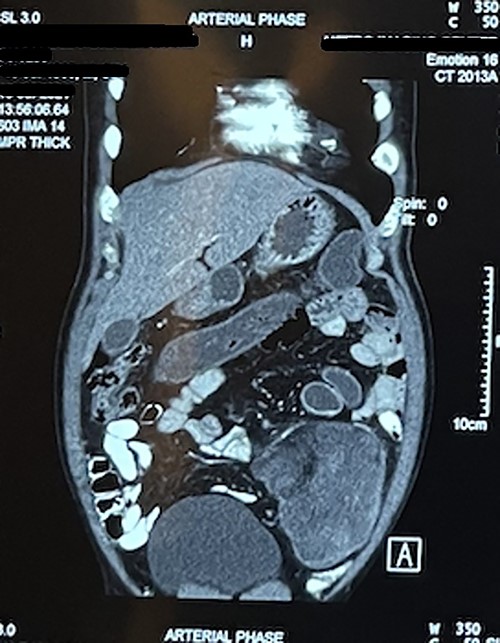

Laboratory test including tumor marker (carcinoembryonic antigen) was normal. Abdominal ultrasonography revealed heteroechoic mass over left iliac fossa with regular borders. Computed tomography (CT) of the abdomen revealed well-defined space-occupying lesion of size 10 × 8.5 × 7 cm at the left iliac fossa. There were no areas of calcification; however, plane between the mass and the bowel was lost in few places suggesting of invasion (Figs 1 and 2).